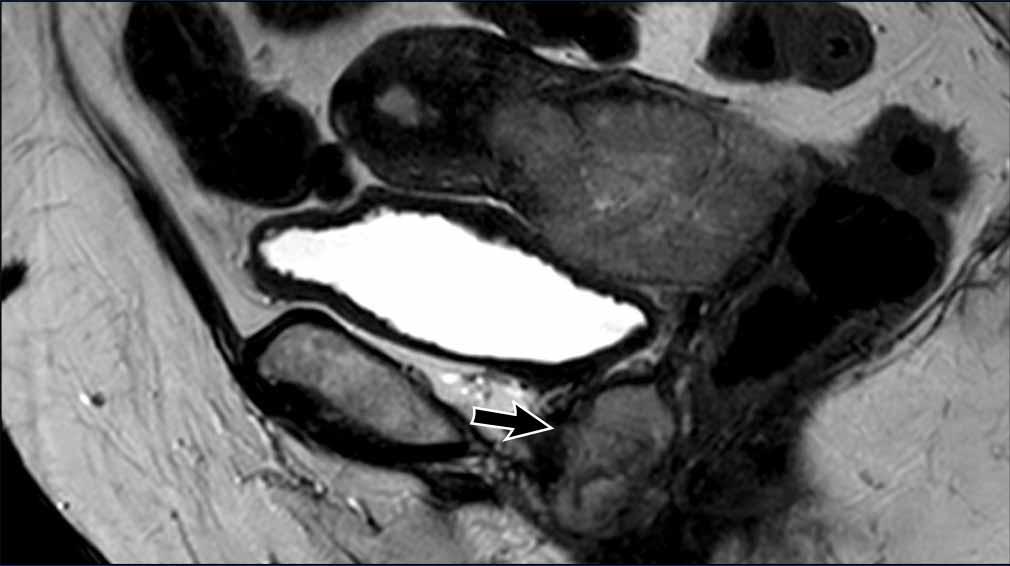

Bẫy chẩn đoán – Khối u lồi vào ống cổ tử cung

Cần phân biệt xâm lấn mô đệm cổ tử cung với khối u lồi vào ống cổ tử cung.

Khối u lồi vào có thể gây giãn rộng ống cổ tử cung kèm theo mỏng mô đệm cổ tử cung do hiệu ứng đè đẩy.

Hình ảnh

Lưu ý rằng không có sự lan rộng thực sự của tín hiệu khối u vào mô đệm cổ tử cung.

Do đó, không có xâm lấn mô đệm cổ tử cung.